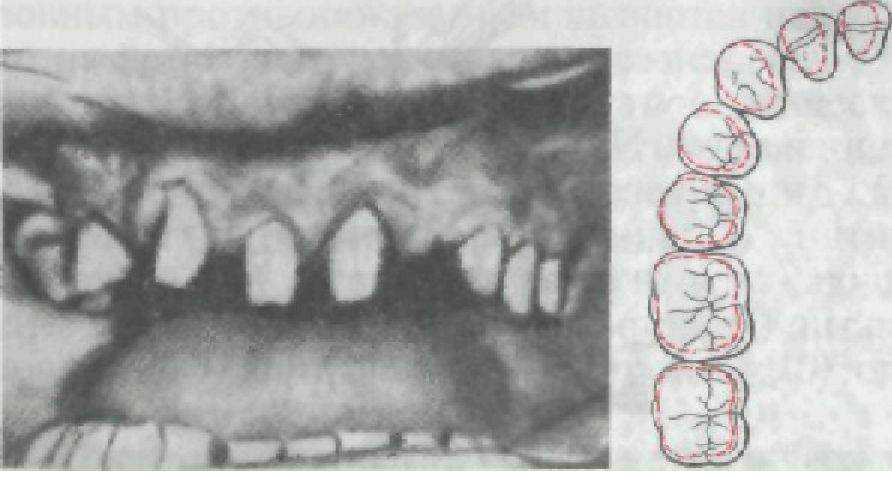

В зависимости от материала различают коронки металлические (сплавы благородных и неблагородных металлов), неметаллические (пластмасса, фарфор), комбинированные (металлические, облицованные пластмассой или фарфором) (рис. 74). В свою очередь металлические коронки по методу изготовления делятся налитые, изготавливаемые отливкой из металла по заранее заготовленным формам, и штампованные, получаемые штамповкой из дисков или гильз.